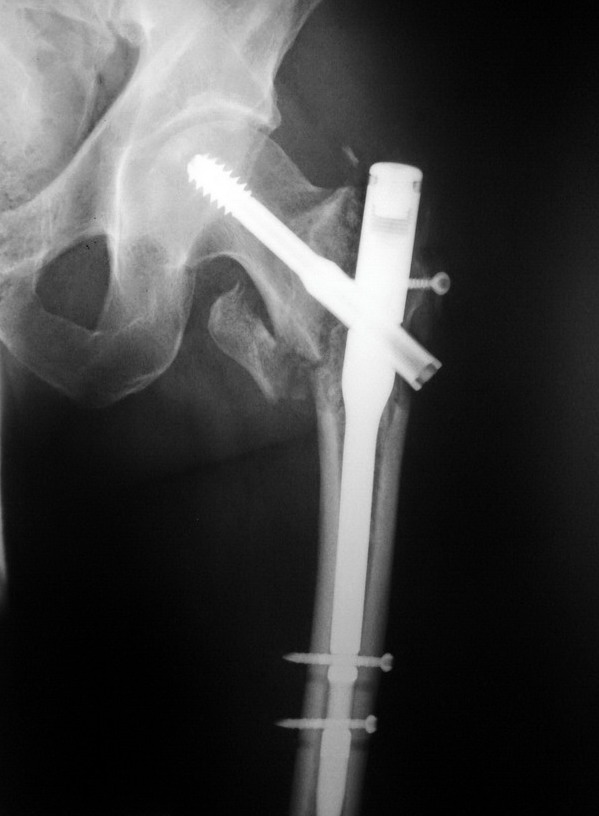

Так стало после реостеосинтеза - два снимка непосредственно сразу после

операции, последний снимок - через 6 мес. Пациент свободно ходит.